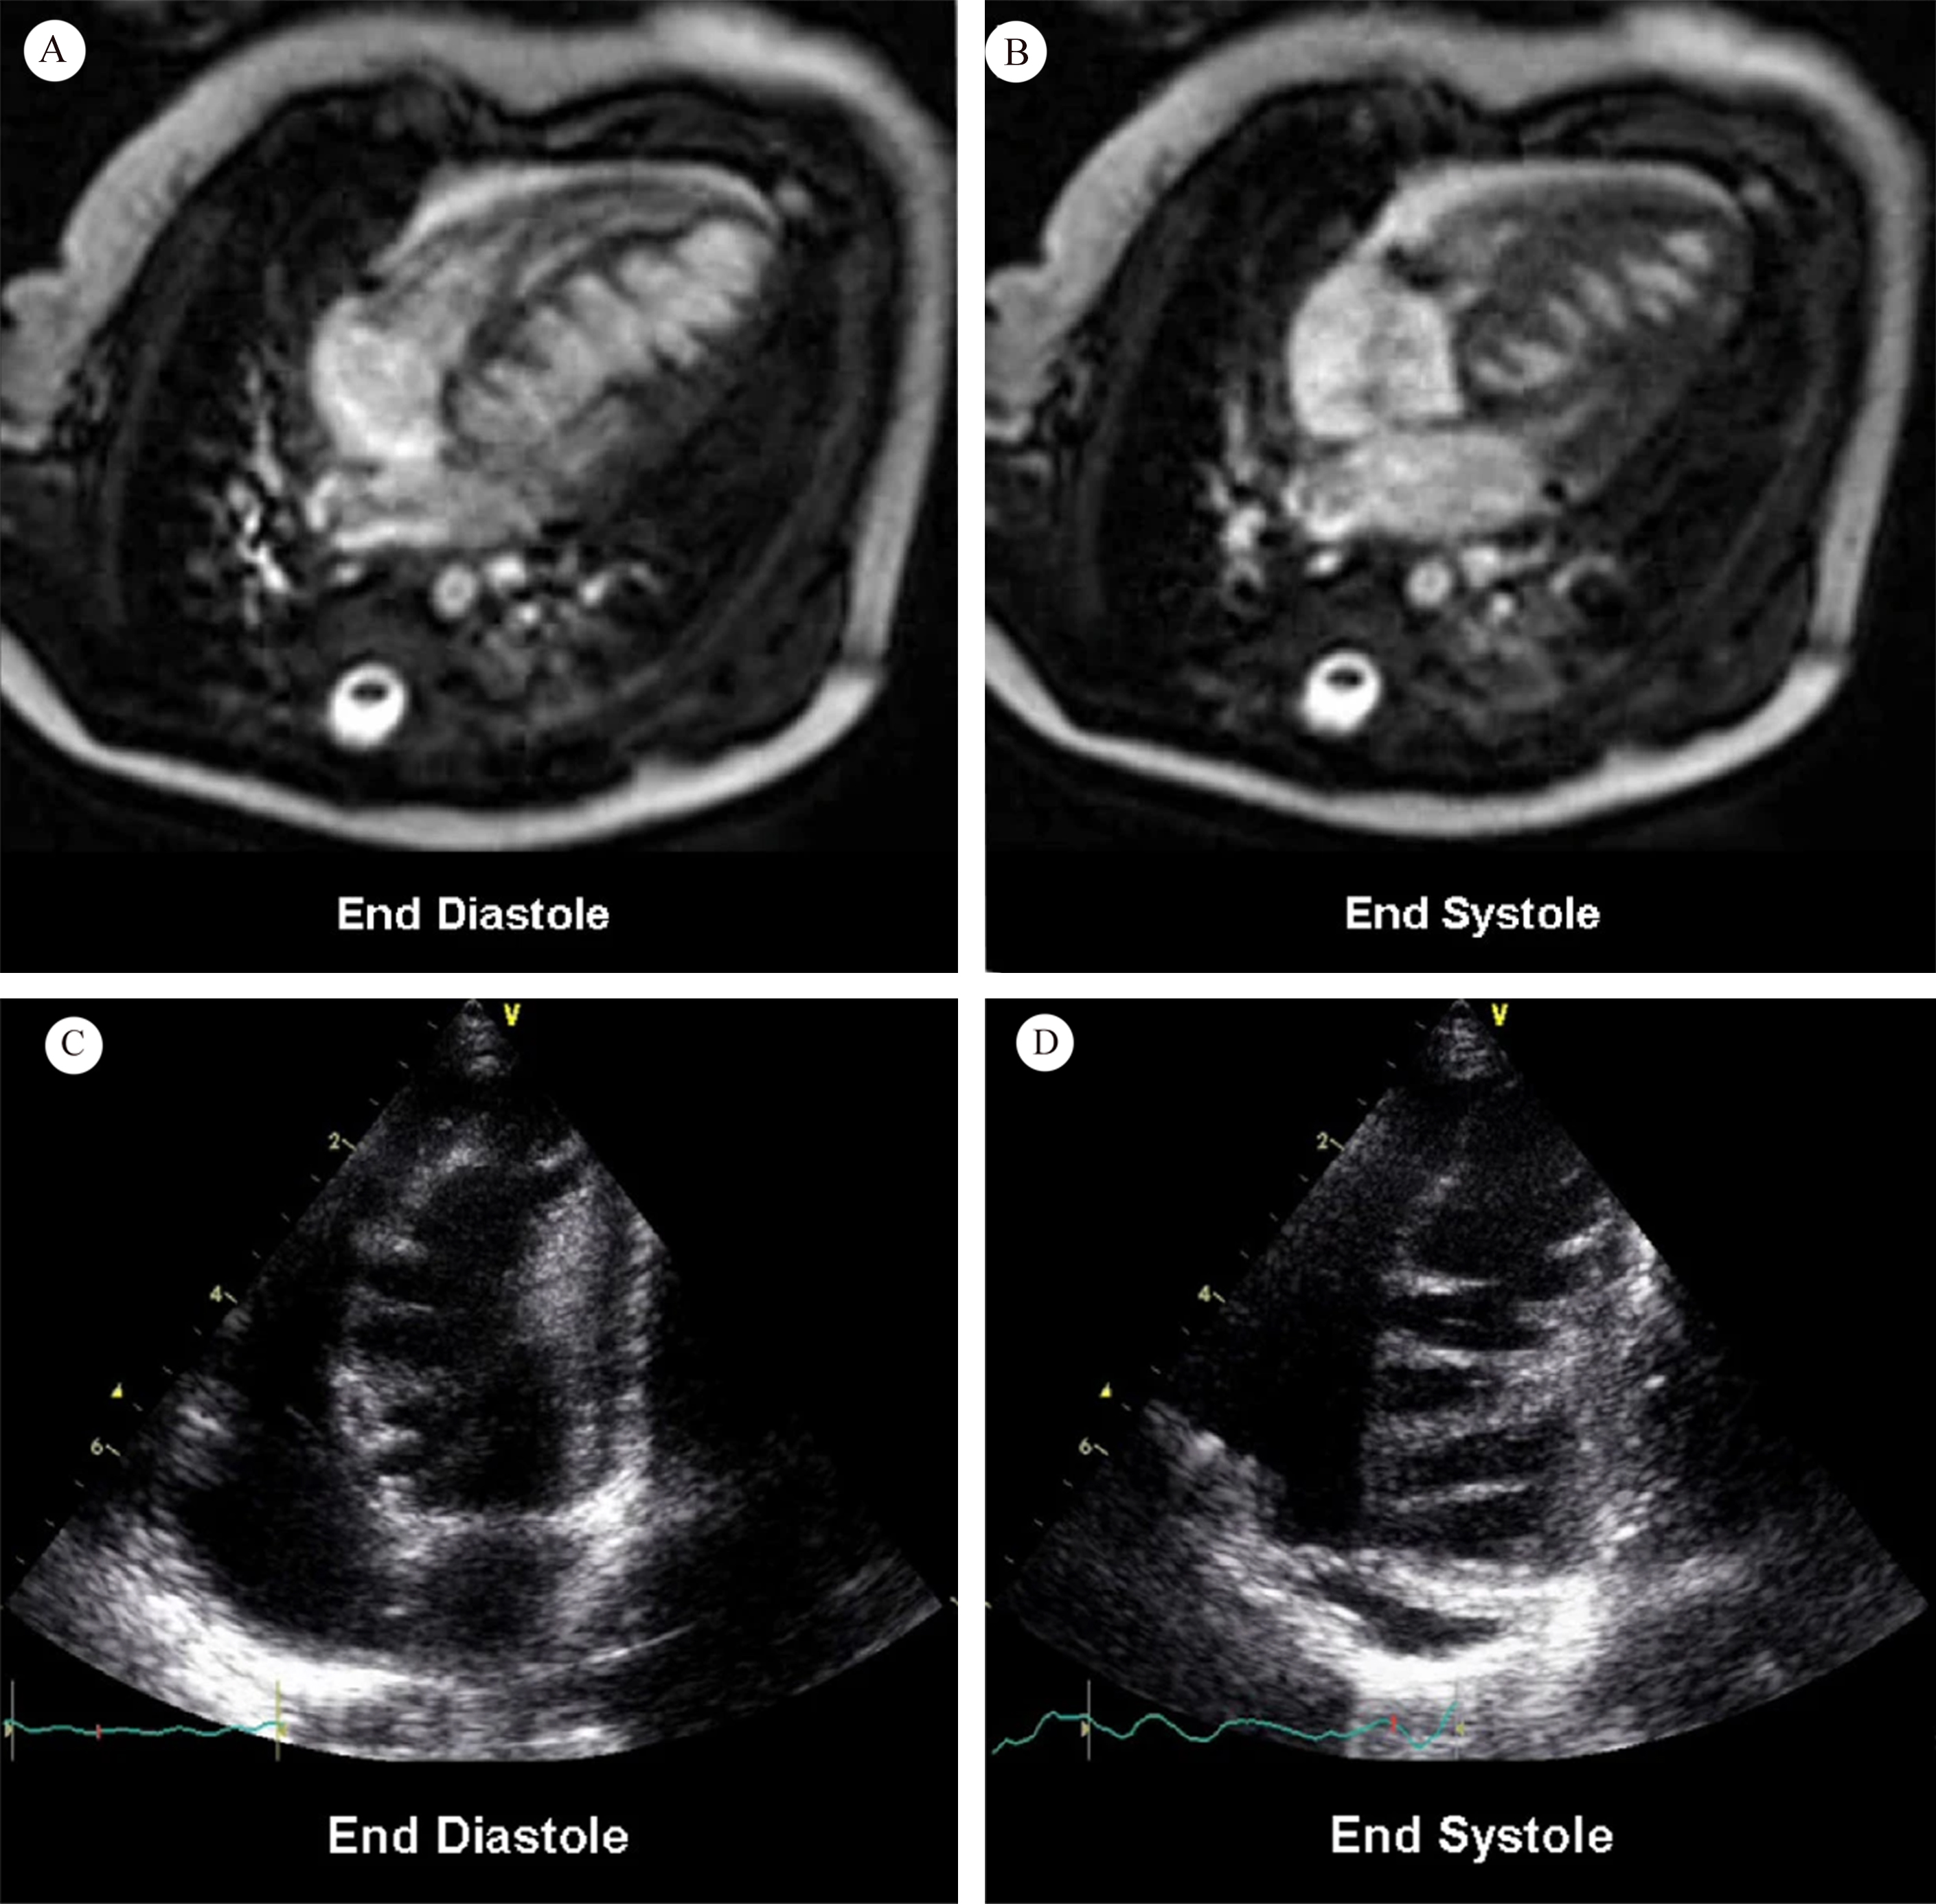

Saw-tooth cardiomyopathy (STC), first discovered in 2009 [1, 2], is a rare form of left ventricular cardiomyopathy, mainly affecting the apex and middle segment of the left ventricular wall and inferior wall. It may be evident in transthoracic echocardiography on admission. In most reported cases cardiac magnetic resonance (CMR) can provide a clearer view of the internal structure of the heart, with multiple dense myocardial protrusions similar to saw-tooth like crypts. These differ from left ventricular noncompaction (LVNC), which is characterized by noncompact myocardium in the layer of finely trabeculated myocardium adjacent to a layer of compacted myocardium [3]. The clinical course of STC ranges from asymptomatic to acute heart failure, and it can also be associated with a variety of cardiac complications. Typical images for STC are shown in Fig. 1 (Ref. [2]), and for LVNC in Fig. 2 (Ref. [3]) for comparison.

Fig. 1.Cardiac magnetic resonance (A and B); transthoracic echocardiography (C and D). Fig. 1A,B show numerous saw-tooth like muscular projections originating from the interventricular septum, some of them being tethered to the inferior LV wall. Fig. 1C,D show numerous saw-tooth like projections originating from the inferior interventricular septum to lateral LV wall (Fig. 1 is cited from Davlouros PA, et al. [2]).